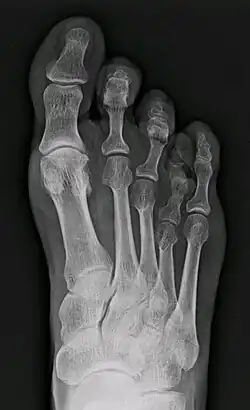

X-ray of congenital brachymetatarsia involving fourth metatarsal bone | |

Brachymetatarsia is a rare malformation that causes one or more toes to be abnormally short. The condition is characterized by a metatarsal arch shortness of more than 5 mm. The condition is more common in females, and the incidence reported in the literature ranges from 0.02% to 0.05%. Brachymetatarsia appears to be the result of epiphyseal plate retardation or premature closure. The etiology may be congenital and idiopathic, posttraumatic, postinfection, iatrogenic, or secondary to a systemic disease such as cancer, sickle cell disease, pseudohyperparathyroidism, Turner's syndrome, Down syndrome, Apert syndrome, athyroidism, or osteodystrophy.[2]

It most frequently involves the fourth metatarsal. If it involves the first metatarsal, the condition is known as Morton's syndrome. Treatment is via a number of differing surgical procedures.[3]